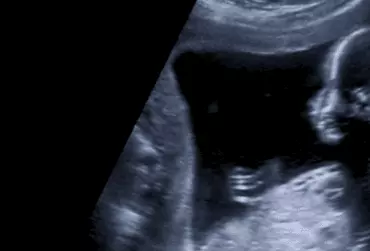

W okresie prenatalnym w przesiewowym badaniu serca płodu rozpoznanie całkowitego nieprawidłowego spływu żył płucnych (TAPRV) jest trudne co tłumaczy bardzo niską wykrywalność tej wady u płodu – około 1,9% (1). Wada należy do bardzo rzadkich wad serca i częstość występowania jej szacuje się na 0,5-2% wszystkich wrodzonych wad serca (WWS) i występuje w przybliżeniu na 8,7/100,000 (2,3) żywo urodzonych noworodków.

Detekcja aberracji chromosomowych w I trymestrze ciąży za pomocą metod ultrasonograficznych i testów biochemicznych

Opracowanie to przedstawia aktualną wiedzę na temat badań prenatalnych w I trymestrze ciąży. Umożliwiają one rozpoznawanie, diagnostykę i leczenie wad wrodzonych, również zespołów genetycznie uwarunkowanych.

Badania mają na celu zapewnienie optymalnych warunków do rozwiązania ciąży a także opiekę nad kobietą będącą w ciąży i noworodkiem. Badania prenatalne wykonywane w I trymestrze ciąży pozwalają na zidentyfikowanie wad wrodzonych płodu oraz określenie ryzyka najczęściej występujących aberracji chromosomowych.